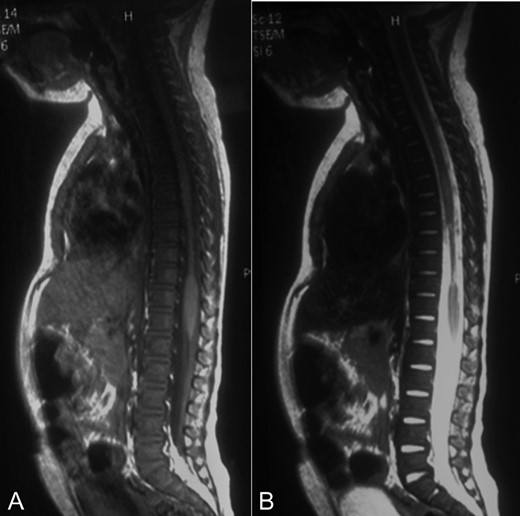

MRI showed a narrowing lesion of the spinal cord from T7 to T10 (Figs 1B, 2A and B).

A-B: A. Sagittal T1 sequence showing a narrowed spinal cord from T7 to T10. B. Sagittal STIR-weighted MRI of the thoracic spine showing chronic appearance of a string-like atrophic cord.

The patient was treated with external immobilization of the spine. At 3-month follow-up she presented with paraplegia, positive bilateral Babinski´s and clonus, complete sensory loss under T7, and bladder and bowel dysfunction.

Our case shows coincidence with the literature, as being a 2-year-old patient who suffered spinal trauma featuring clinical-radiological dissociation. The main difference is that she presented with lower limb neurological deficit due to the thoracic localization of the lesion. Although in our case the diagnosis was 20 days post-trauma, we believe that her MRI pattern corresponded to a type 4.